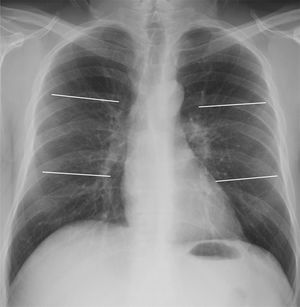

The first quantification system (6A) consisted of dividing each lung into three fields: upper, middle and lower (Fig. 1). According to this division, the extension of pulmonary opacities was classified as mild if only one field was affected, moderate if there were opacities in 2–3 lung fields, and severe if more than 3 fields were affected.

Posteroanterior chest X-ray demonstrating division into 6 lung fields (quantification systems 6A and 6B) by two horizontal lines: upper lung field (from vertices to lower margin of the aortic knob), middle (lower margin of aortic knob to the middle third of heart border) and lower (middle third of heart border to costophrenic sinuses).

The second quantification system (6B) divided both lungs into the same six lung fields as 6A. In this case, mild extension corresponded to 1 or 2 affected lung fields, moderate extension to 3–4 fields and severe extension to 5 or more fields.